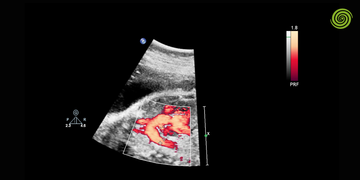

La ecografía obstétrica es un estudio de ultrasonido orientado a la evaluación del embarazo en sus distintas etapas. Su objetivo principal es monitorear el desarrollo fetal, evaluar estructuras anatómicas y detectar posibles complicaciones.

A diferencia de la ecografía ginecológica general, este estudio se enfoca en el feto, la placenta y el entorno intrauterino.

Papel del transductor obstétrico

La calidad de las imágenes y diagnósticos depende en gran medida del transductor utilizado.

El transductor obstétrico abdominal suele operar a frecuencias que permiten buena penetración en etapas avanzadas.

En etapas tempranas, puede requerirse transductor transvaginal para mayor resolución.

La selección adecuada del transductor influye directamente en la precisión diagnóstica.